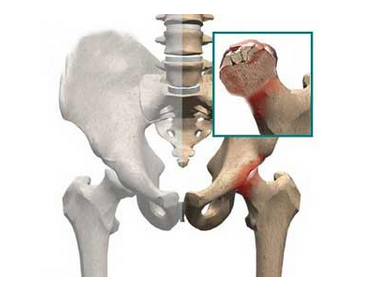

股骨头坏死又称股骨头无菌性坏死,或股骨头缺血性坏死,是骨坏死的一种。股骨头局部血运不良,引发股骨头血液循环障碍,从而使得股骨头进一步缺血、坏死、骨小梁断裂、股骨头塌陷的一种病变。股骨头坏死的原因西医大致概括为外伤、激素使用过量、酗酒、先天性发育、职业病以及其他疾病后期并发症等,现代医学目前尚无有效的治疗药物

中医称股骨头坏死为“骨蚀”。本病有多种病因,包括意外的创伤、慢性劳损、六淫之邪侵袭、七情内郁、饮食不节所致内损或用伐损之药。这些原因均可损伤气血,造成气血运行紊乱而出现瘀滞,加之机体体质虚弱,抗病能力低下,肝肾精血不足,导致肌肉筋骨失荣而发生痹痛,致使骨质疏松,也是股骨头缺血坏死的潜在原因。病变涉及肝、脾、肾。肾为先天之本,主骨生髓,肾健则髓生,髓满则骨坚;反之,则髓枯骨萎,失去应有的再生能力。肝主筋藏血,与肾同源,二者荣衰与共,若肝脏受累,藏血失司,不能正常调节血量,血液营运不周,营养难济,是造成股骨头坏死的重要病机。脾主运化,脾失健运,则筋骨肌肉皆无气血以生。